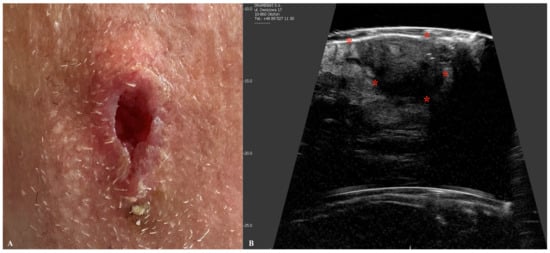

6. Mycosis Fungoides

| Mycosis Fungoides | Presence of a subepidermal low-echogenic band (SLEB). Useful in monitoring disease progression and response to therapy. |